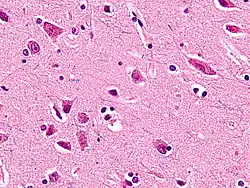

Микрофотография с изображением веретенообразных нейронов в поясной извилине. Окраска гематоксилином и эозином; луксолом.

Веретенообразные нейроны или нейроны фон Экономо (названы в честь их первооткрывателя Константина фон Экономо[1]), описанные в 1929 году, являются особым классом нейронов. Для них характерно большое веретенообразной формы тело, постепенно сужающееся в единичный апикальный аксон на одном конце и единственный дендрит на противоположном конце. Кроме того, что у других типов нейронов чаще встречается большое количество дендритов, полярная форма веретенообразных нейронов уникальна. Они найдены только в двух очень ограниченных районах головного мозга гоминид: в передней поясной коре (ППК) и во фронтоинсулярной коре. Недавно эти нейроны были найдены и в дорсолатеральной префронтальной коре мозга человека[2]. Веретенообразные клетки также есть в мозге горбатых китов, финвалов, косаток, кашалотов[3][4] , афалин, серых дельфинов, белух,[5], африканских и индийских слонов.[6]